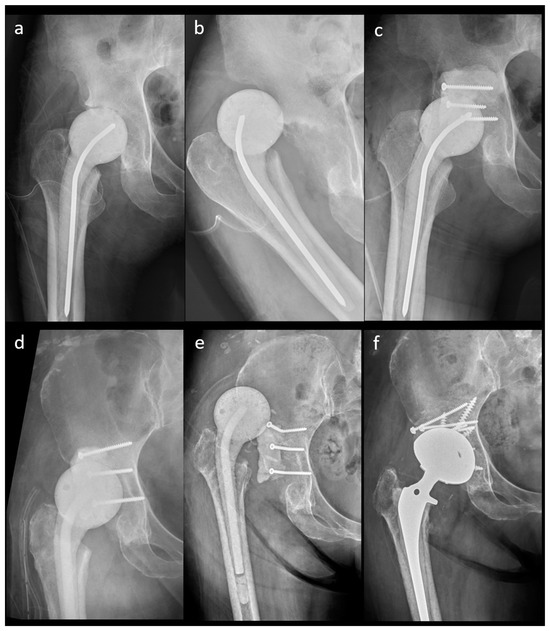

Fracture of cement spacers may occur in either multiple small diameter Hip Spacer Complications The use of “functional” spacers may allow patients to return to daily living while optimizing their health for revision surgery. Temporary spacers used in the staged revision of a hip prosthetic joint infection (pji) have been associated with several mechanical. We aimed to evaluate the clinical outcomes of different spacer. The aim of this retrospective study was to identify and. Hip Spacer Complications.

Figure 2 from Mechanical complications and infection control comparison Hip Spacer Complications The use of “functional” spacers may allow patients to return to daily living while optimizing their health for revision surgery. Temporary spacers used in the staged revision of a hip prosthetic joint infection (pji) have been associated with several mechanical. The aim of this retrospective study was to identify and evaluate complications after hip spacer implantation other than reinfection. We. Hip Spacer Complications.

Figure 3 from Mechanical complications and infection control comparison Hip Spacer Complications Temporary spacers used in the staged revision of a hip prosthetic joint infection (pji) have been associated with several mechanical. We aimed to evaluate the clinical outcomes of different spacer. The use of “functional” spacers may allow patients to return to daily living while optimizing their health for revision surgery. The rehabilitation program following hip spacer implantation emphasizes early, controlled. Hip Spacer Complications.